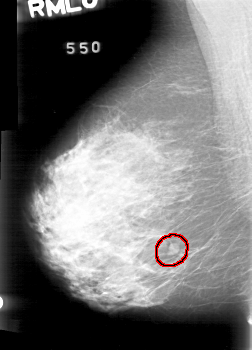

D_4022_1.RIGHT_MLO

RIGHT_MLO LINES 5236 PIXELS_PER_LINE 3766 BITS_PER_PIXEL 12 RESOLUTION 43.5 OVERLAY

FILE: D_4022_1.RIGHT_MLO.OVERLAY

TOTAL_ABNORMALITIES 1

ABNORMALITY 1

LESION_TYPE MASS SHAPE ROUND MARGINS OBSCURED

ASSESSMENT 0

SUBTLETY 5

PATHOLOGY BENIGN

TOTAL_OUTLINES 1